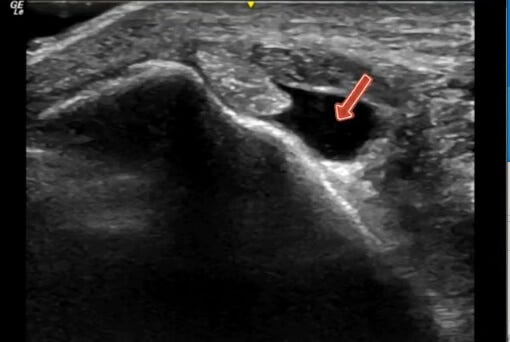

Anecoico

"Es una imagen negra propia de los líquidos, debido a la ausencia de reflexión de los ultrasonidos."

Es decir, el Punto 0 de la Escala de Grises. Fácil de identificar y que pueden corresponderse con sangre, hematomas, quistes, líquido sinovial...

Como podemos observar en la imagen, es un exceso de líquido del músculo tibial posterior.